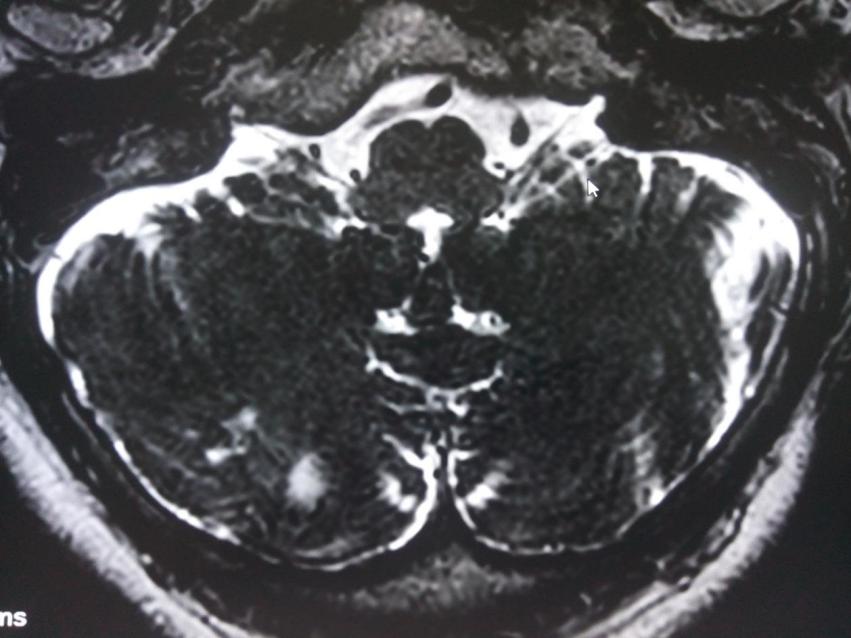

生长性颅骨骨折继发癫痫手术案例

患者赵某,男性,14岁(入院时年龄) 3年前开始出现发作性肢体抽搐,伴半身后仰,双眼上翻,偶有意识丧失,多数情况下不伴意识障碍,每次发作持续约1-2分钟,发作前无明显先兆,发作后头痛明显,早期未服药...【详细】